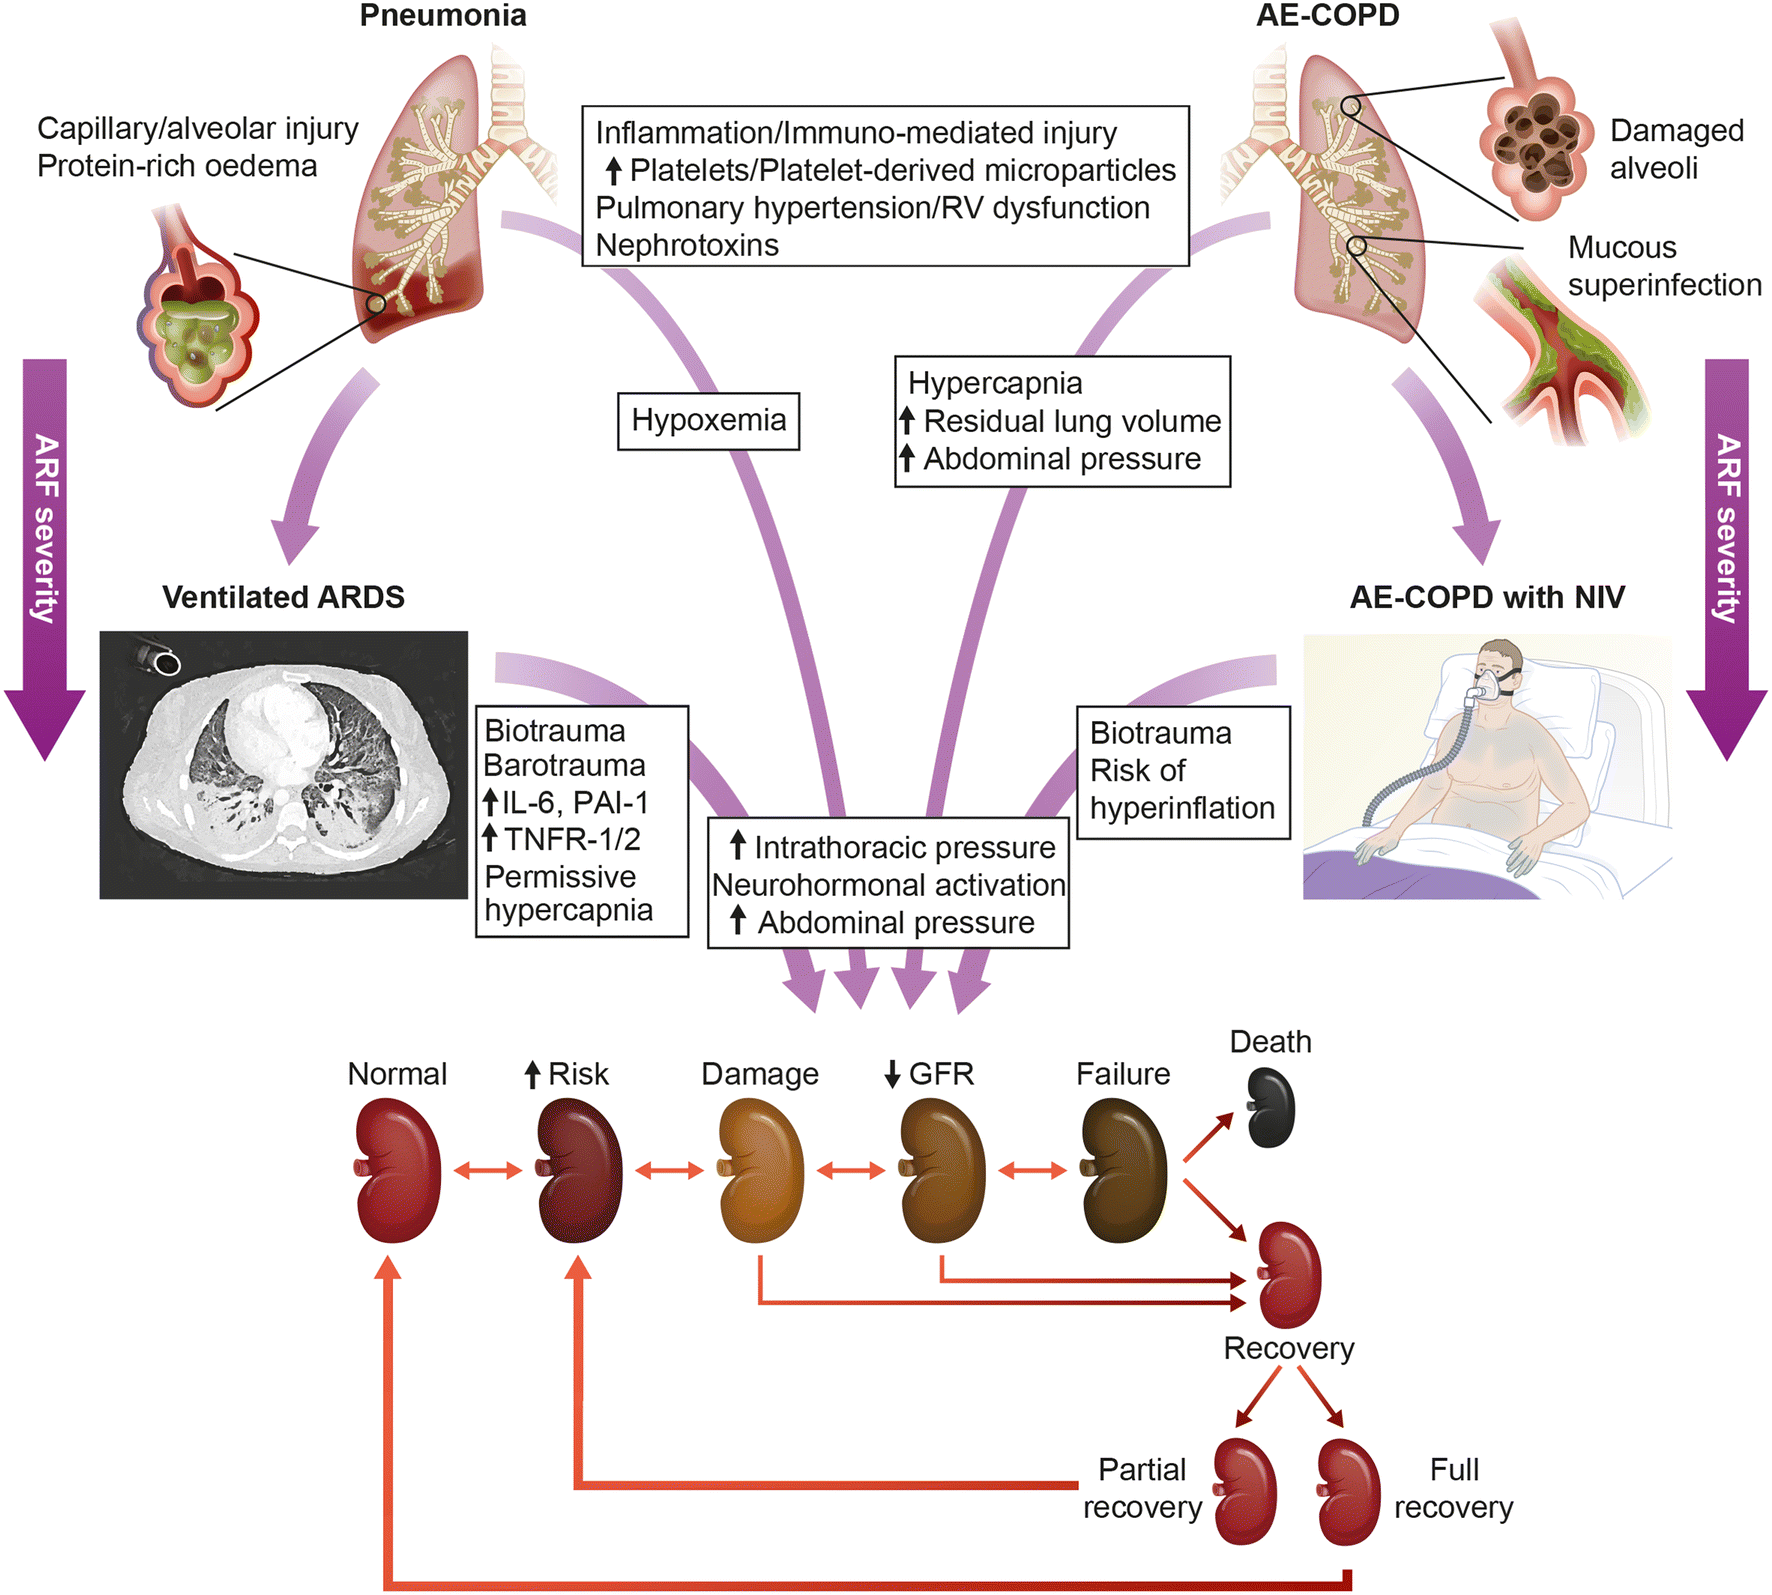

Anhand von langzeit-epidemiologischen Studien und Daten von Intensivstationen sowie Publikationen in Fachjournalen seit 1964, wurden Ergebnisse analysiert; auch tierexperimentelle Studien wurden berücksichtigt. „Bekannt ist bisher, dass eine sowohl eine akute Lungen- als auch Nierenschädigung zu vermehrt Komplikationen aber auch erhöhter Sterblichkeit bei kritisch kranken Patientinnen und Patienten führen kann. Eine sich zusätzlich entwickelnde akute Nierenschädigung im Rahmen eines akuten Atemnotsyndroms kann die Krankenhaussterblichkeit auf fast 60 Prozent erhöhen“, weiß Michael Joannidis, Leiter der Gemeinsamen Einrichtung für Internistische Intensiv- und Notfallmedizin an der Medizin Uni Innsbruck. Es ist jedoch nach wie vor nicht vollständig geklärt, wodurch diese Komplikationen bedingt sind. Einerseits werden von der geschädigten Lunge entzündungsfördernde Botenstoffe freigesetzt, die zu einer Nierenschädigung führen können, andererseits können auch die durch die Lungenerkrankung bedingte Störungen in der Sauerstoffversorgung zu einer Einschränkung der Nierenfunktion führen. „Darüber hinaus wissen wir, dass bei einer mechanischen Beatmung der Lunge Einschränkungen noch erhöht werden können“, so Joannidis.

Umgekehrt kann es jedoch auch im Rahmen einer akuten Nierenschädigung zu einer zunehmenden Schädigung und Funktionseinschränkung der Lunge kommen. „Dies kann zum Beispiel durch einen Flüssigkeitsüberschuss bedingt sein, wenn die Niere aufgrund ihrer Schädigung eine adäquate Flüssigkeitsausscheidung nicht mehr aufrechterhalten kann. In weiterer Folge kann dies ein Lungenödem zur Folge haben“, erklärt Intensivmediziner Joannidis. Durch entsprechende vorsichtige Flüssigkeitsbilanzierung beziehungsweise Unterstützung der Flüssigkeitsausscheidung mit harntreibenden Medikamenten oder Nierenersatztherapie (Dialyse) könne dieser Komplikation, so ein Ergebnis der Untersuchung, vorgebeugt werden. Des Weiteren konnten verschiedene Effekte von extrakorporalen Systemen, wie eine „künstliche Niere oder Lunge“, auf die Organfunktionen aufgezeigt werden. „Insbesondere die Kombination von extrakorporalen Systemen stellt Ärztinnen und Ärzte vor neue Herausforderungen und Fragestellungen, wodurch auf diesem Gebiet sich einige neue Forschungsfragen ergeben haben“, sagt Michael Joannidis. So konnten insgesamt mit Ergebnissen der Untersuchung sowohl Empfehlungen für die direkte Patient:innenenversorgung als auch weitere Fragestellungen für zukünftige Forschungsschwerpunkte formuliert werden.